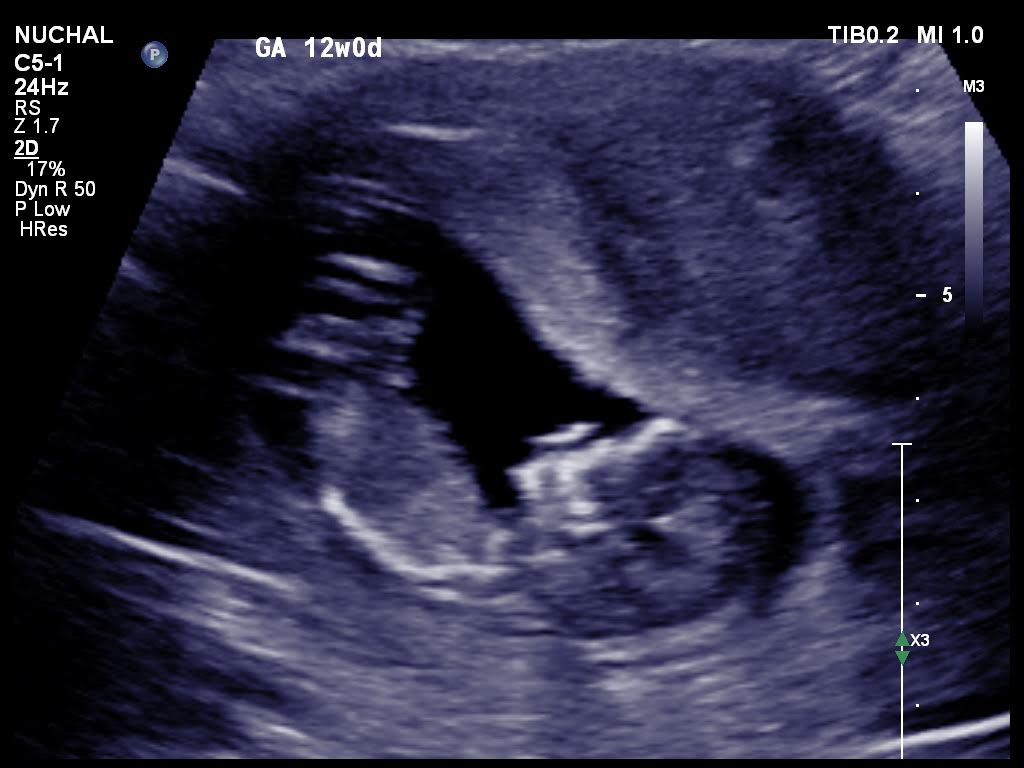

Is it possible for anybody to suggest the gender please from these 12 weeks ultrasound scans.